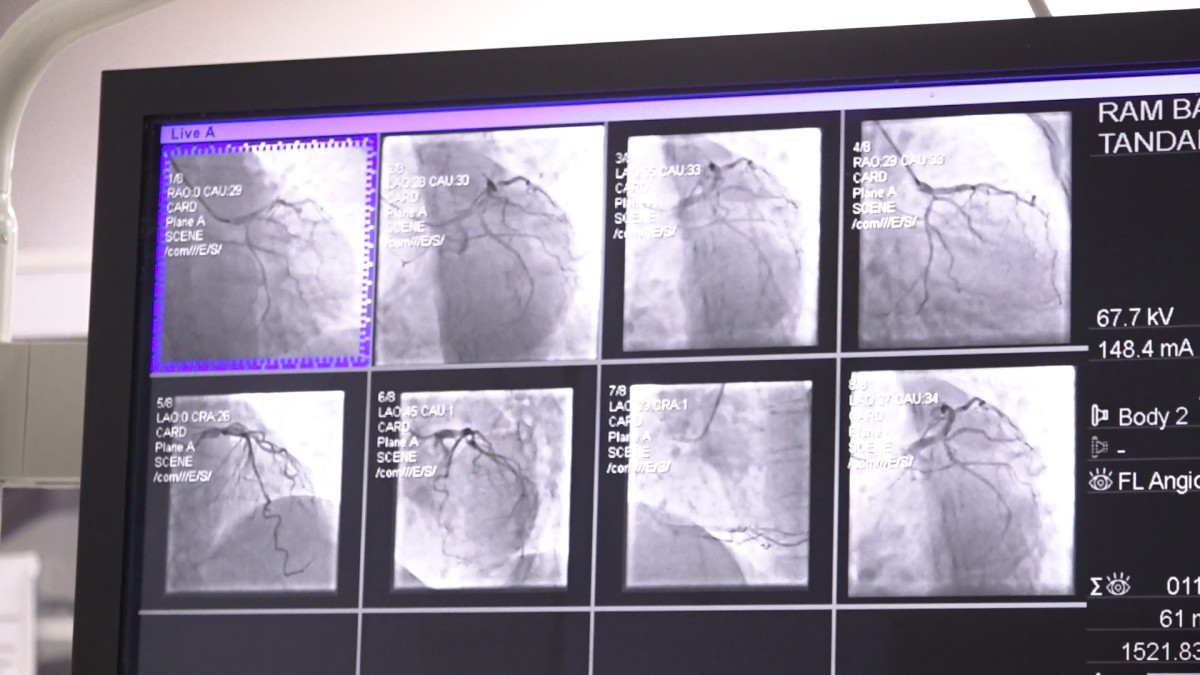

प्रा. ढुङ्गानाकाअनुसार क्याथ ल्याव एक विशेष प्रकारको अत्याधुनिक एक्स–रे मेसिन हो । जसले धड्किरहेको मुटु र नशागत समस्याहरूको जाँच तथा उपचार गर्न सकिन्छ । डा. ढुङ्गानाले क्याथ ल्यावमा हृदयको नशा परीक्षणका लागि हात वा खुट्टाको नशामा सानो सुई (सामान्यतः स्थानीय एनस्थेसिया) मार्फत पाइप (क्याथेटर) प्रवेश गराइने बताउनु भयो । यो प्रविधिमार्फत हृदयका विभिन्न रोगहरू—जस्तै नशा ब्लकेज, जन्मजात मुटुका प्वाल, भल्बको साँघुरो वा अन्य हृदयसम्बन्धी जटिलताहरूको छिटो र सुरक्षित उपचार सम्भव भएको प्रा. ढुङ्गानाले बताउनु भयो । यस प्रक्रियाले धेरै जटिल रोगहरूलाई सहज र सुरक्षित बनाएको उहाँले जिकिर गर्नुभयो ।

बाइ–प्लेन प्रविधिः दुवै फोटो एकैचोटि

काठमाडौं मेडिकल कलेजले प्रयोग गर्दै आएको क्याथ ल्याव ‘बाइ–प्लेन’ मोडेल भएकाले यस प्रविधिले एकैचोटि दुईवटा फोटो खिच्नसक्ने जसका कारण डाई र विकिरणको मात्रा कम हुने डा.ढुङ्गानाले बताउनु भयो । उहाँकाअनुसार ‘यसले बिरामीको मिर्गौलामा पर्ने प्रभाव घटाउँछ र चिकित्सकको काम पनि सहज बनाउँछ’ । नेपालमा करिव एक दशक अगाडि भित्रिएको यो प्रविधि काठमाडौं मेडिकल कलेजमा करिव तीन वर्ष देखि उपलब्ध छ । क्याथ ल्यावको प्रयोगले बिरामीलाई डर लाग्ने अवस्था कम हुने, छुट्टि तत्कालै दिन सकिने र महत्वपूर्ण रूपमा समय बचत हुने डा.ढुङ्गाना बताउनु हुन्छ ।

उहाँले भन्नुभयो, ‘काठमाडांै मेडिकल कलेजमा शुरुवात गरेको लगभग तीन, साढे तीन वर्ष भयो र नेपालमा त धेरै वर्षदेखि छ । नेपालमा १०/१५ वर्षदेखि नै यो सेवा विभिन्न सेन्टरहरुमा उपलब्ध छ । तर यो मेसिन चाहीँ हाम्रो अत्याधुनिक टाइपको, हामी बाइ प्लेन भन्छौं, एकैचोटि यसले चाहीँ दुईवटा फोटो खिच्छ । अरु मेसिनमा के हुन्छ भन्दा खेरि हामीले दुई चोटि फोटो खिच्नलाई एउटा डाई हुन्छ त्यो डाइ दिनुपर्ने अनि एक्स—रेको विकिरण बढी लिनुपर्ने हुन्थ्यो भने यसमा चाहीँ एकैचोटी दुईवटा फोटो खिच्ने भएको हुनाले एकैचोटी डाई पठाएर दुईवटा फोटो लिन सकिन्छ । त्यसले अलि सहज पनि हुन्छ । हामी गर्ने मान्छेलाई पनि विकिरणको प्रभाव कम पर्न जान्छ । कतिपय बिरामीको मृगौलामा समस्या आउन सक्ने समस्या सेफ हुन्छ ।’